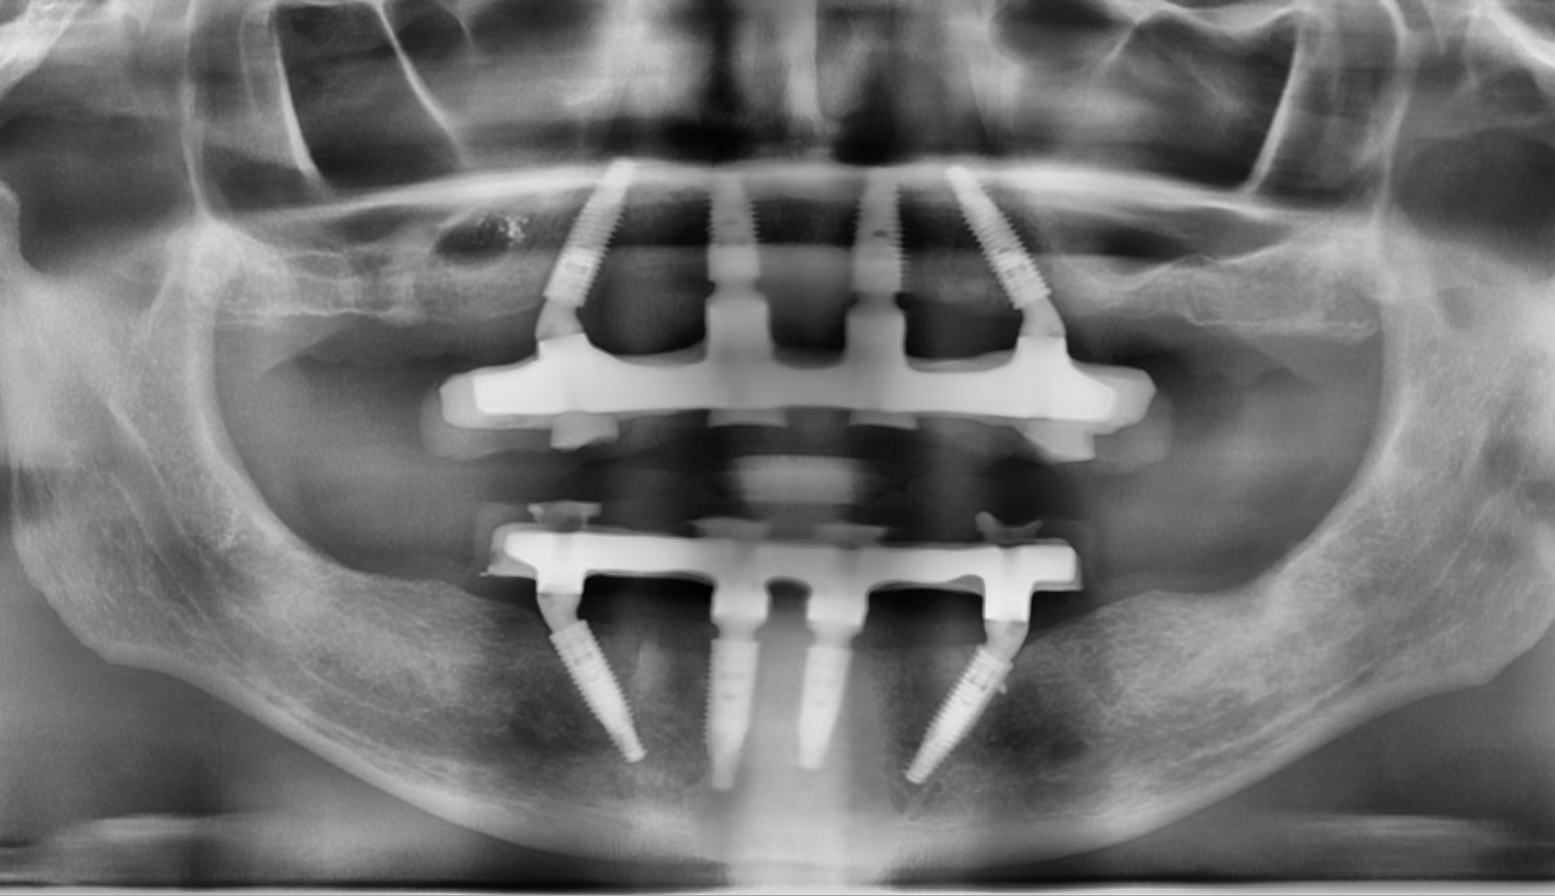

- сложная имплантация (например, методики «All-on-4/6» или установка имплантатов Zygoma)

Примеры наших работ